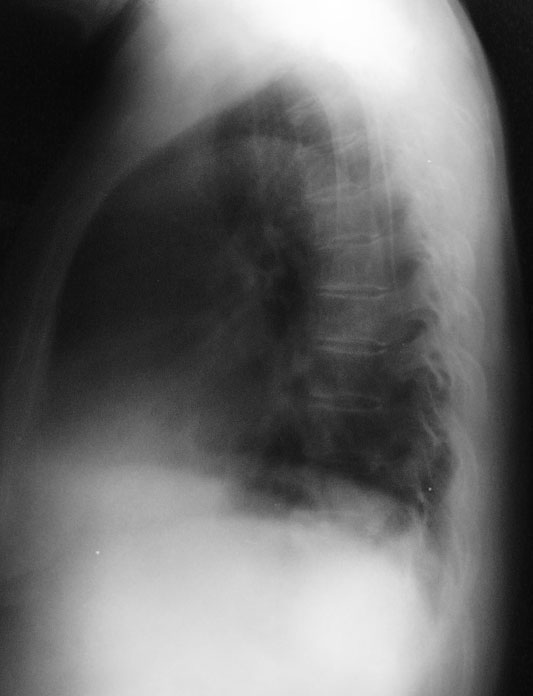

标题: X7067:胸部平片

女,68岁,咳嗽、咯血(血丝)一周。余其它状况良好~~

左侧肋膈角变钝

未见明显异常,做个ct看有没有局灶性支扩。

胸部平片未见异常。

平片阴性,ct可能阳性.

平片未见明显异常,建议hrct看有否支扩表现。

左侧少量胸腔积液;左侧膈肌略抬高,建议ct检查。

体胖老年妇女,肋膈角处可能是乳房影,胸部未见明显异常改变,有症状,建议ct进一步检查,以免误诊